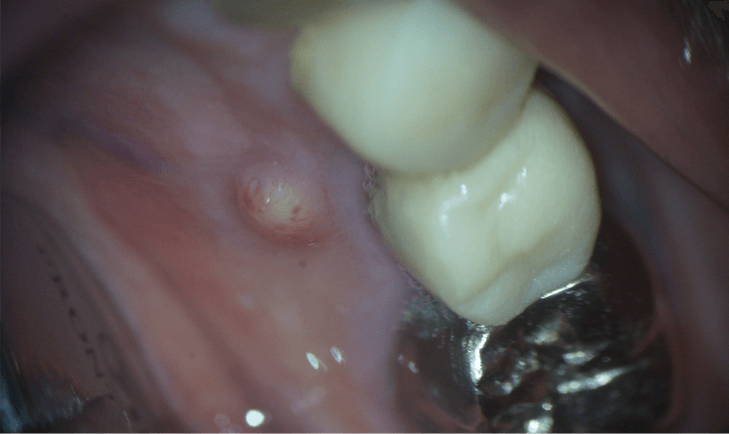

歯茎も腫れています。

この時点で、通常の根の治療では汚れがすべて取りきれないと判断し、歯根端切除術を行うことになりました。